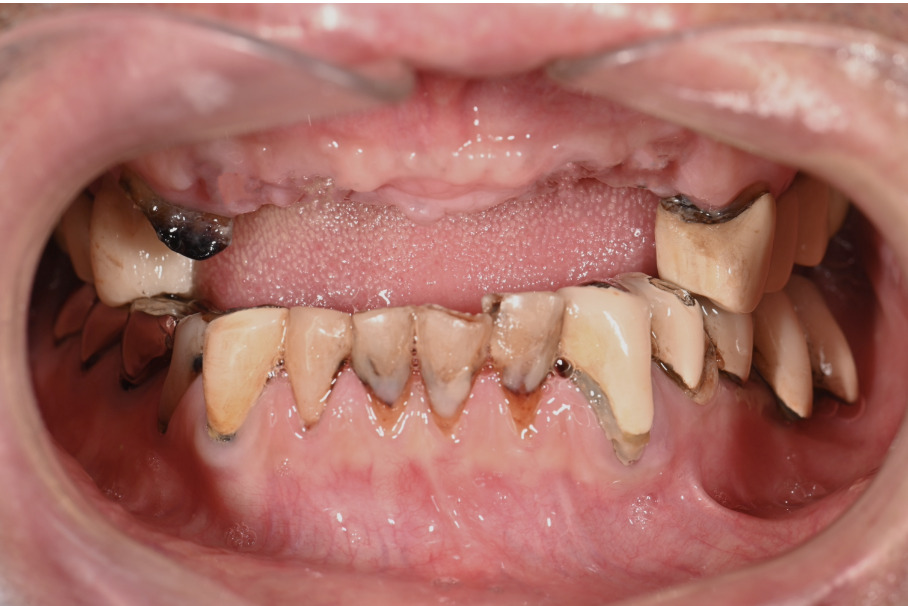

| 主訴 | 歯がグラグラして噛めない |

|---|---|

| 治療内容 | 上顎、下顎に対するインプラント治療 |

| 治療期間 | 1日 |

| 治療費 | 409万2千円 |

| 治療 リスク | 最終的な歯が入るまでは仮歯になります。 |